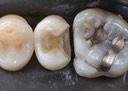

Kyle Chock #30 amalgam removal

Kyle Chock #30 prep

Mark Chun #2 pre-op